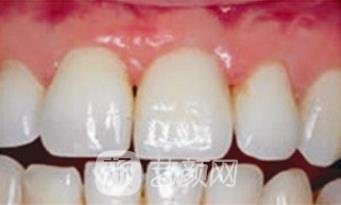

原本的牙齿就不是很齐,因为一次篮球比赛还缺失了一颗犬牙,简直是雪上加霜的事情,好在家里面的人得知了我的情况,给予了资金上的支持,让我安装一颗质量好一些的牙齿,所以挑选了德国的种植牙,虽说有一点小贵,但种植后的效果还是很满意的。